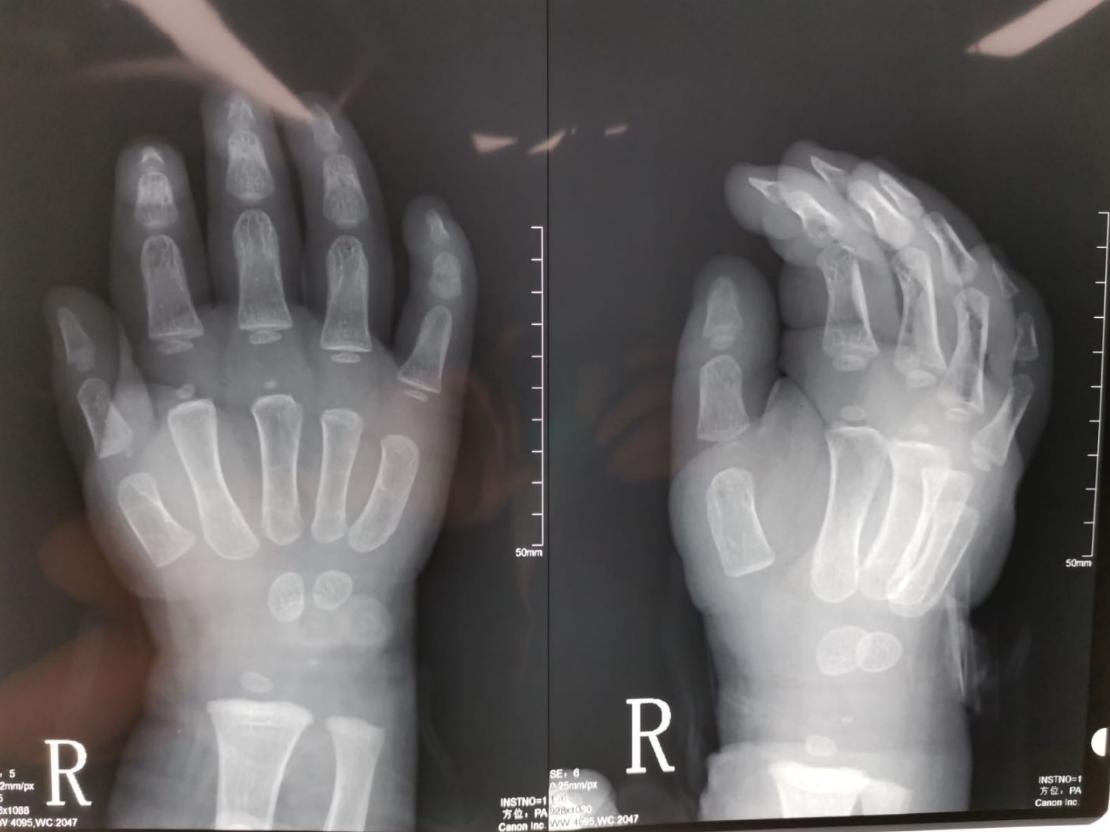

病例7:看到这样的手之后,很多人的第一反应就是怎么只有三根手指,能不能通过手术把三根手指变成五根。其实对于这个孩子的情况,还是要先把并指分开,分开之后可以考虑四根手指,因为通过对比X线片子,我们发现只有三根手指的这个手的第二根手指的指骨和掌骨都比好的那个手指的指骨和掌骨粗,这就意味着这是一个完全的复杂并指。

右手x线

左手x线

如果家长有需求,我们可以给这个孩子进行第二次分指,把三根手指变成四根,分指之后粗细有一定的保障,但是五根手指的可能性不大,哪怕从脚上移植,外观、功能和协调性可能都达不到我们想要的效果,所以四根手指可以探讨,五根意义不大。